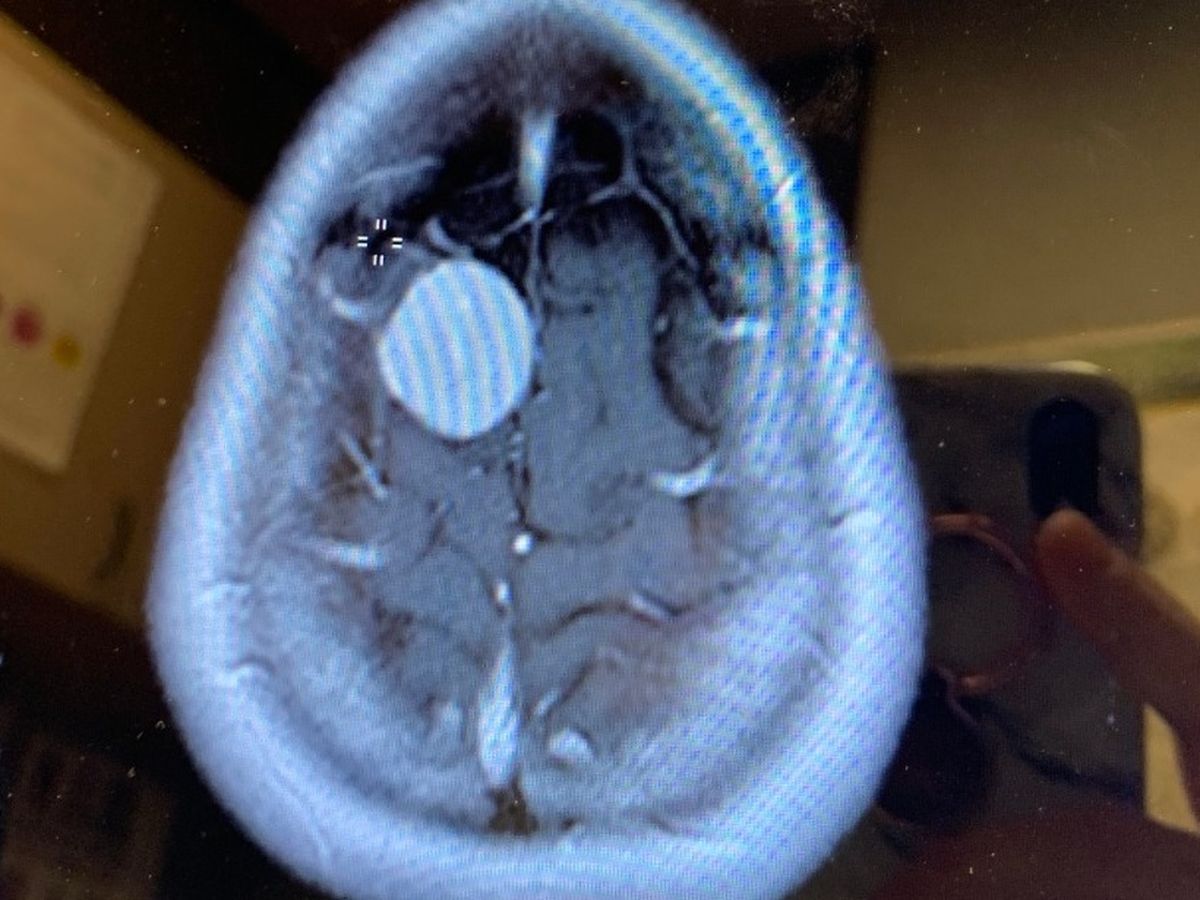

Laurie Worman has been diagnosed with a brain tumor called a Menegenoma. The tumor is growing at a very fast rate and is located on the top of her head (frontal bone), on the outside of her brain (outer cortex), and under the skull. She has a right posterior frontal parafalcine dural mass.